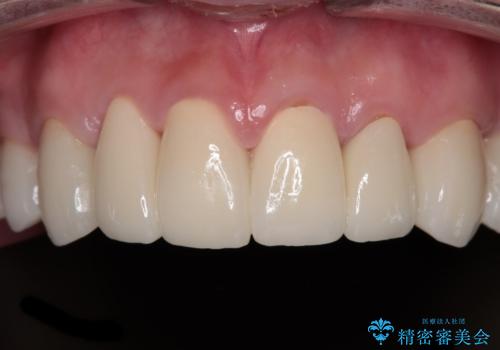

酸蝕歯でボロボロの歯の審美歯科治療 矯正治療も併用して、美しい口元へ

- 一時期の拒食症に伴い歯が酸で溶けてボロボロになってしまったとのことで来院された患者様です。

酸によりエナメル質の大半が溶けており、下顎前歯以外は酷いむし歯のような状態でした。

矯正治療終了後に、残った歯をオールセラミッククラウンにて補綴治療を行うこととしました。

途中来院が困難な時期があったり、歯周外科処置を行って治癒を待ったりと、治療期間は長くなりましたが、初診時とは比べものにならないくらいきれいに仕上げることができました。